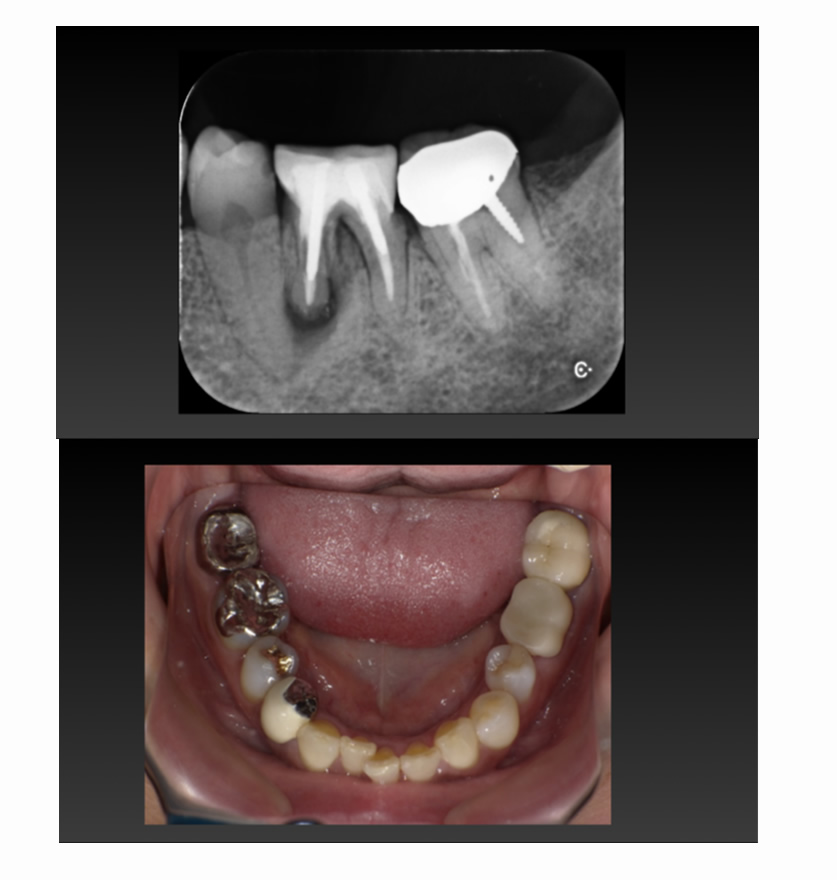

05 症例

歯が割れ、咬むと痛いのでインプラントにしたい

Before

After

| 治療内容 | 歯が割れていて咬むと痛いのでインプラント希望 |

| 患者さま | 60代女性 |

| 主訴 | 咬むと痛いのでインプラントにしたい |

| 治療期間(目安) | 3ヶ月 |

| 治療費(税込:目安) | ¥518,100 |

| リスク | 術後に多少の痛みや腫れが出ることがある。歯肉退縮がおきると、歯と歯肉の間に隙間が生じることがあります。 |